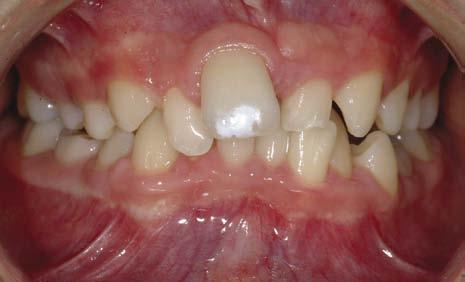

Dentoalveolar trauma

Trauma to the primary maxillary incisors can result in displacement of the tooth into the developing tooth bud of the permanent successor. Damage to the crown or dilaceration of the root can occur, resulting in failure of eruption and impaction of the tooth. Loss of a permanent incisor due to trauma can result in space loss and shift in the dental centre line in crowded dentitions (Fig. 1.15).

Figure 1.15 Loss of UL1 through trauma with subsequent space loss and a shift in the dental centreline.